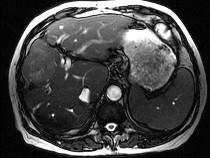

问题 男40岁肝区疼痛,消瘦乏力,腹部包块,AFP阳性,MR检查如图,最佳的诊断是哪一项()

选项 A.肝脓肿 B.肝血管瘤 C.肝腺瘤 D.肝肉芽肿 E.肝癌

答案 E